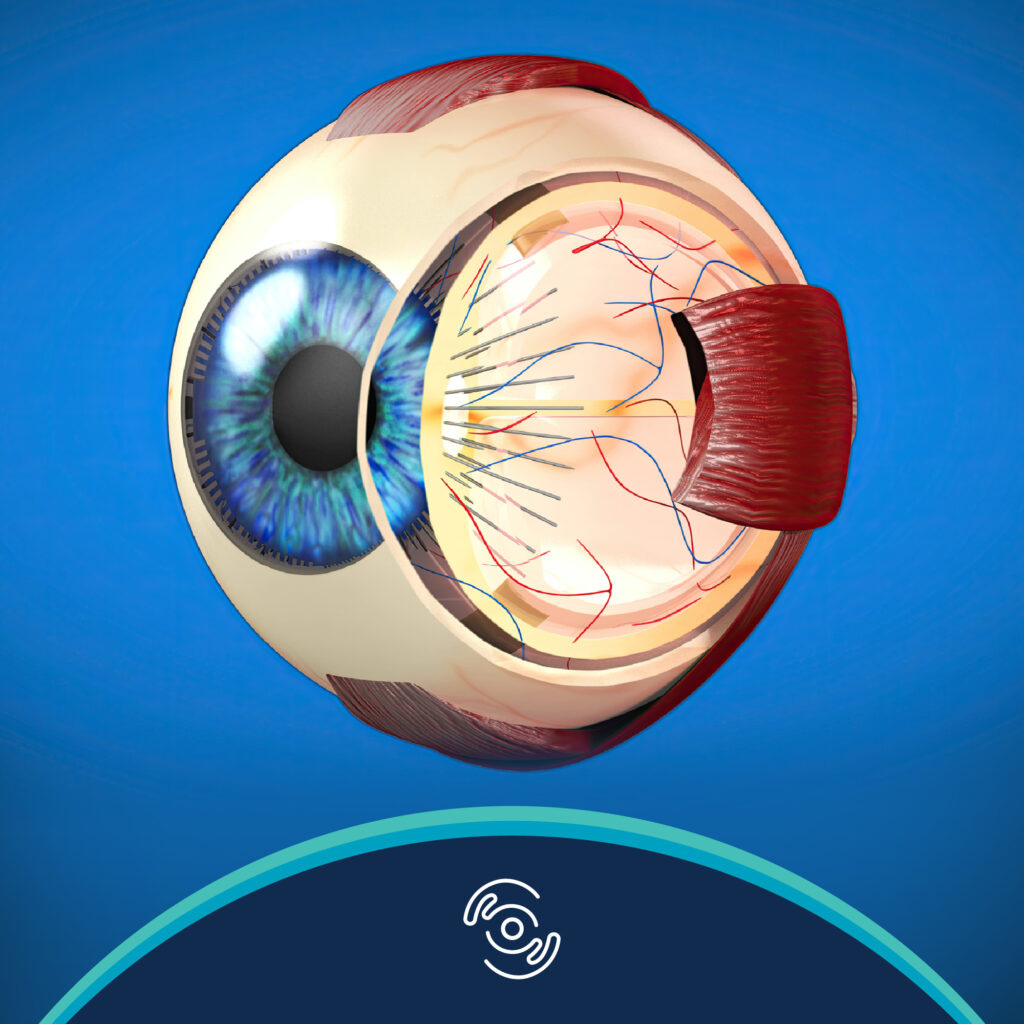

Duong, HV (2013). Corneal Embryology. In Copeland and Afshari, Principles and Practice of Cornea (Two Volume Set), 1st ed

Duong, HV (2013). Corneal Physiology. In Copeland and Afshari, Principles and Practice of Cornea (Two Volume Set), 1st ed. Jaypee Brothers Publisher. New Delhi, IN.

Duong, HV. Eye Globe Anatomy. Medscape Reference. Updated 9 November 2017.

Duong, HV. Visual System Anatomy. Medscape Reference. Updated 9 November 2017.